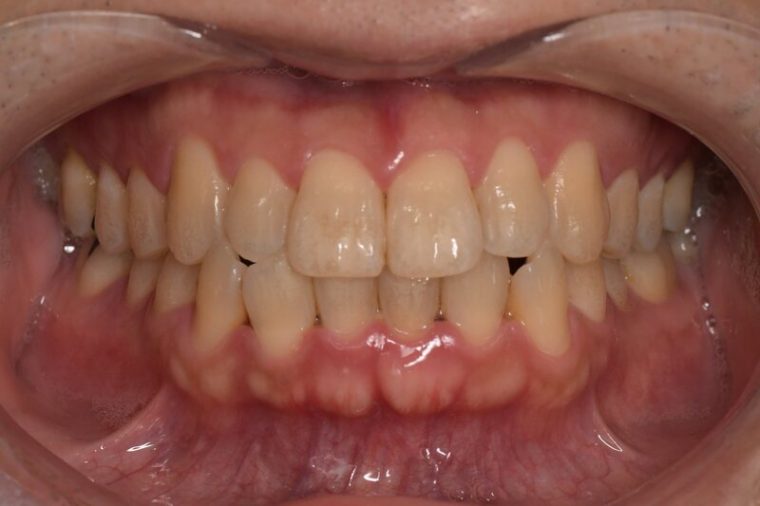

重度歯周病

特徴

歯周炎の段階です。

• 歯がグラつく、抜け落ちそう

• 歯ぐきからの出血が長期間、またはずっと続く

• 歯ぐきから膿がでる

• 口臭が強い

• 歯ぐきが下がって歯と歯の隙間が目立つ

重度歯周病の歯ぐきの写真

歯科医院でのクリーニング、歯ぐきを切開しておこなう歯石除去や歯の骨を補填する手術などあらゆる治療方法を用いて治療をおこないます。歯を残すことは前提ですが、リスクになりうる歯を抜歯するご相談をおこなうこともあります。

グラグラになった歯にブラシの毛先を当て磨くことは簡単ではありません。また歯ぐきの中に入り込んだ汚れは歯ブラシで取りきることができないため歯科医院での歯周病治療、クリーニングを受けるようにしましょう。